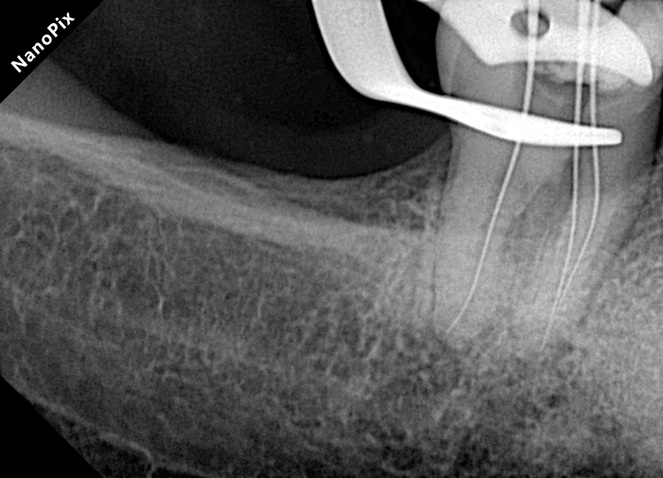

Paso 1 | Negociación

Limas K #10 con técnica de fuerzas balanceadas para alcanzar la longitud de trabajo. Esta fase inicial permitió establecer un camino seguro en conductos posiblemente calcificados o con anatomía compleja.

Paso 2 | Limpieza

Patency apical para lograr la máxima remoción de detritos. La patency fue clave para evitar el empaquetamiento de tejido necrótico y mejorar la desinfección del sistema de conductos radiculares.

Paso 3 | Glide Path

Lima 016 del sistema Súper Flexi para crear una vía de deslizamiento segura y predecible. Esta lima ofreció la flexibilidad necesaria para mantener la anatomía original durante la creación del glide path.